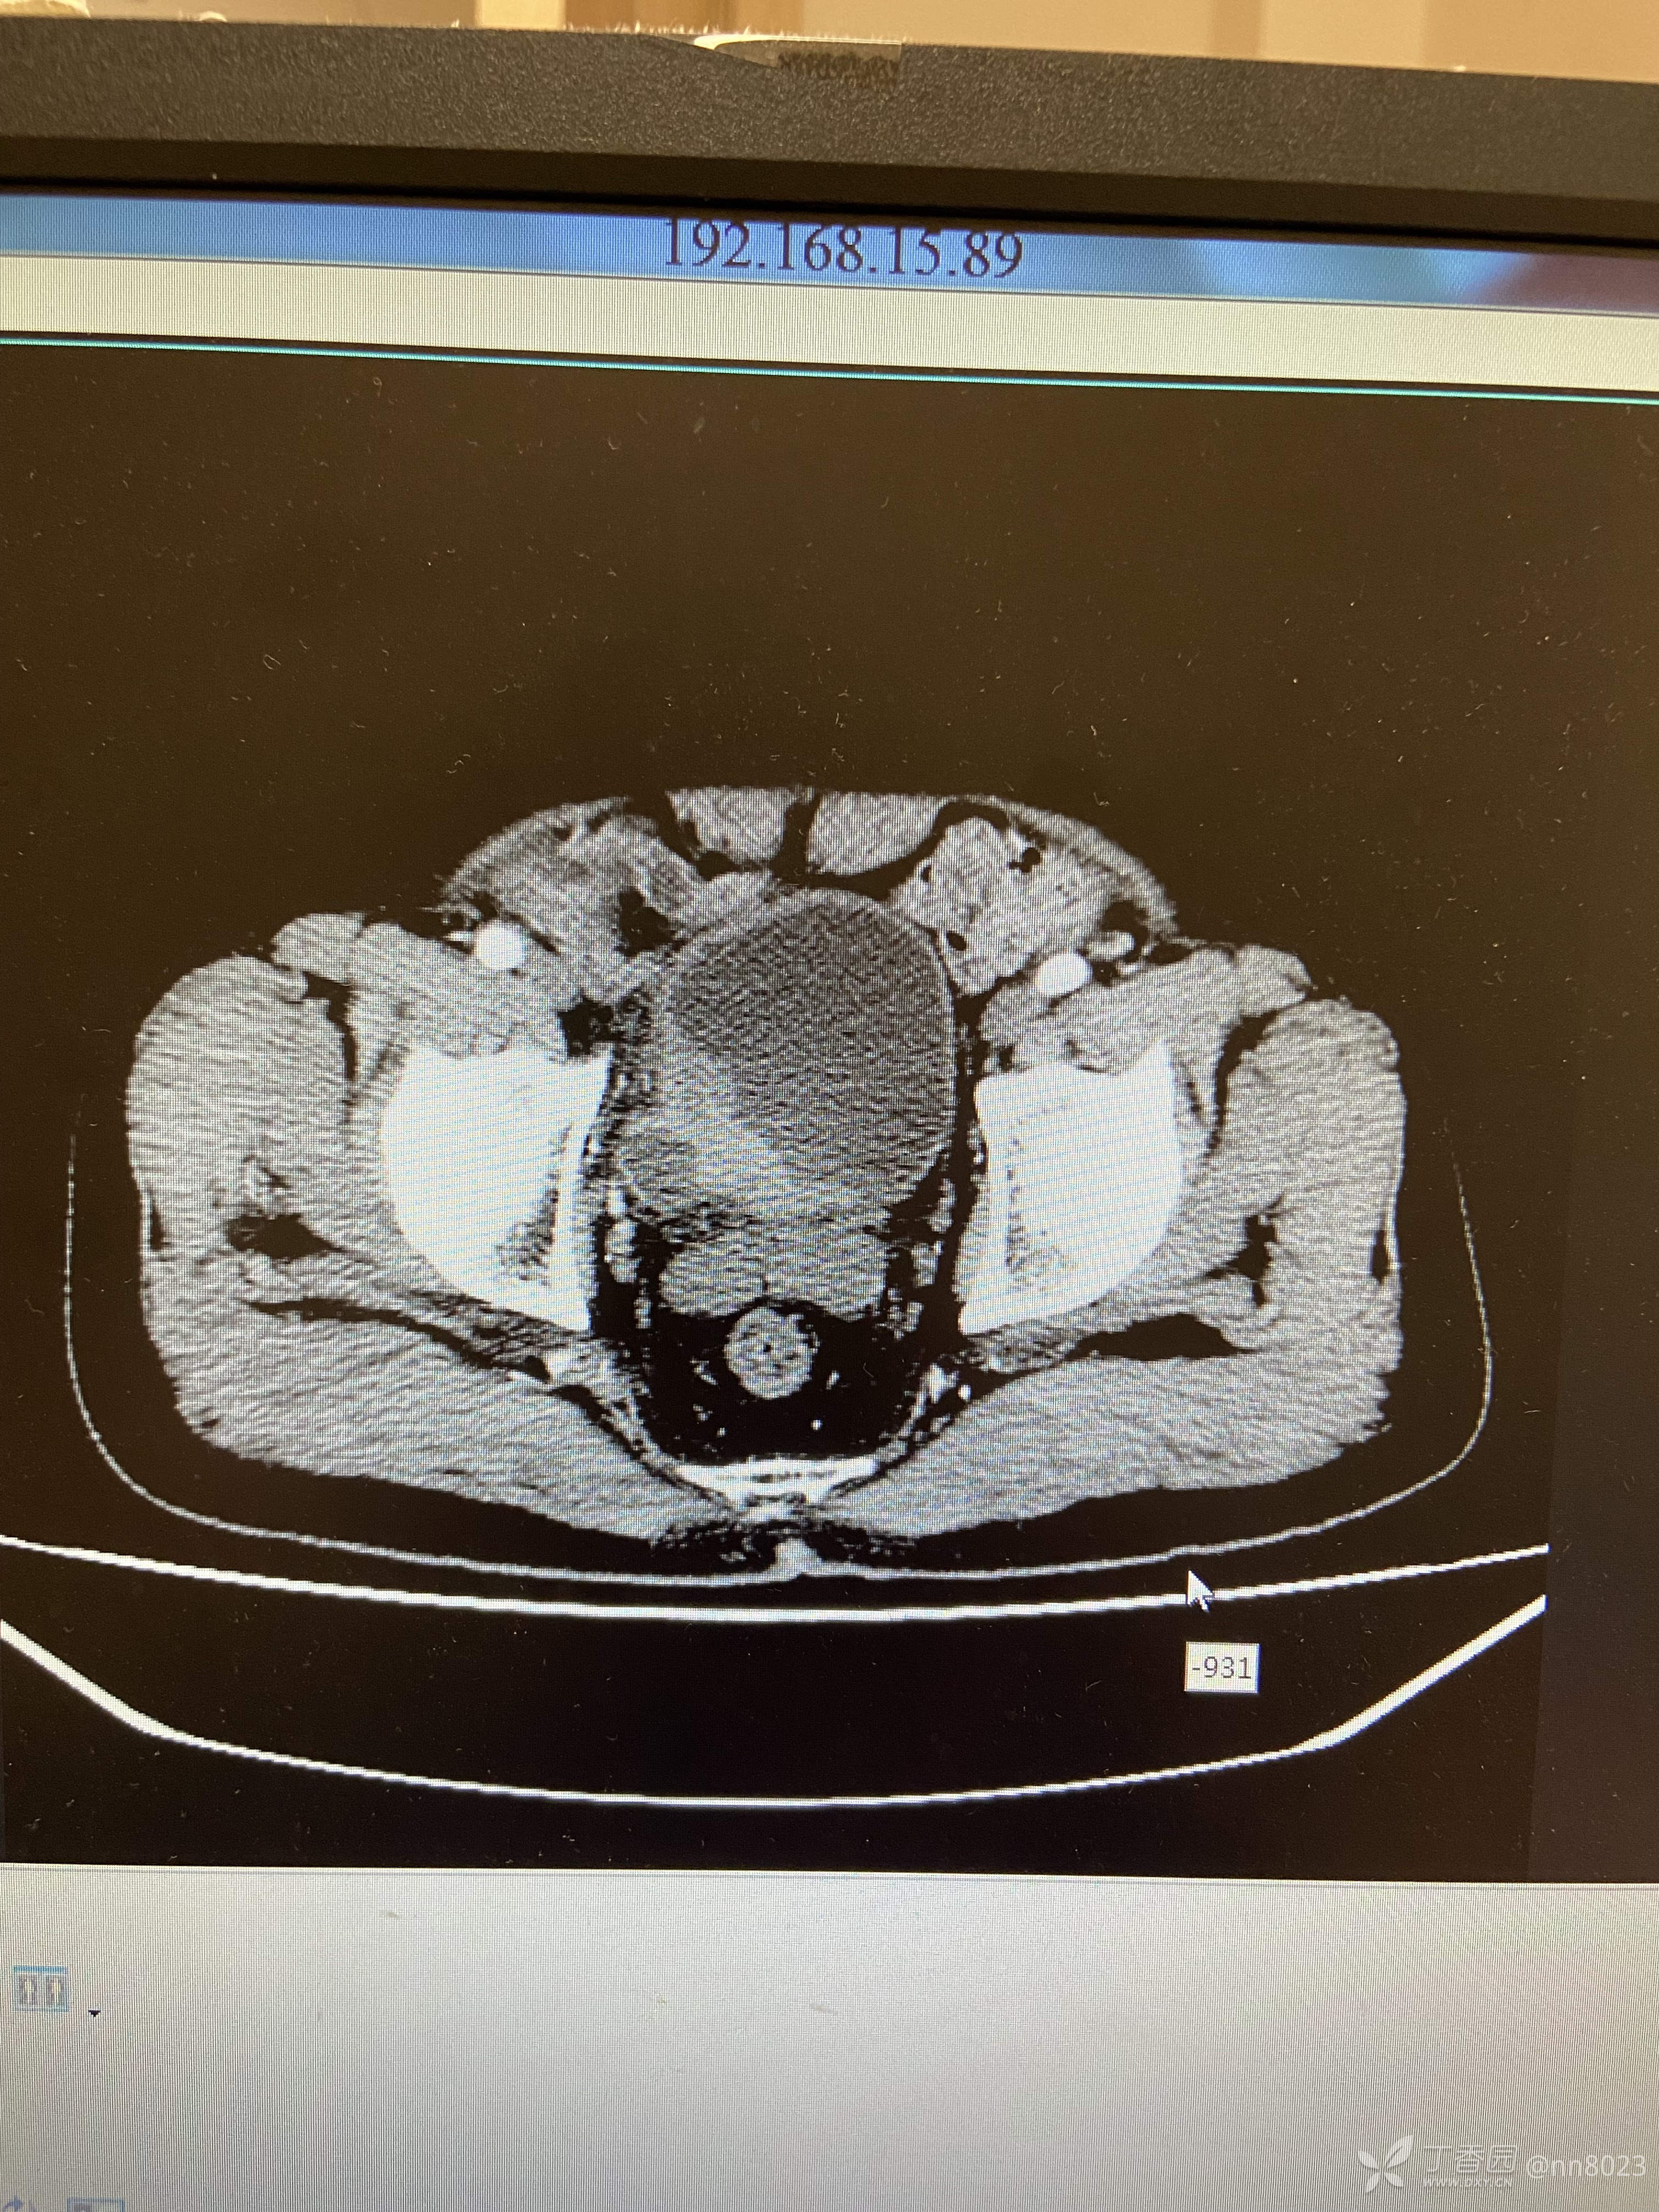

xiaospring +3 丁当66岁男性患者,因尿频尿痛于当地医院检查,彩超提示膀胱占位,完善增强CT

后面又做了经输尿管镜检查(视频见下一个帖子),输尿管末端狭窄,其上方输尿管扩张明显,未见明显占位性病变,膀胱内组织已取活检,待病理。